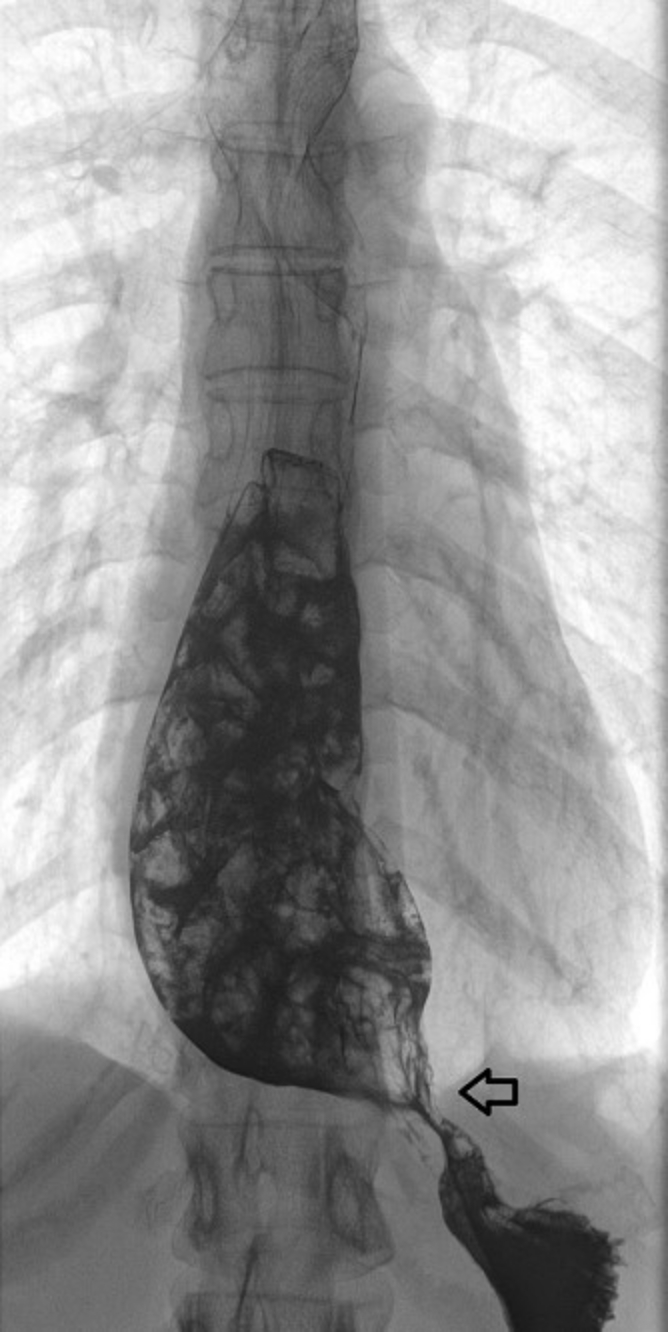

食道X光攝影呈現食道管腔擴大,賁門處呈「鳥嘴狀」狹窄,顯影劑不易流入胃內。而食道機能壓力檢查顯示在吞嚥時食道體從上到下呈同步收縮,賁門壓力高出正常值且吞嚥時舒張不完全,綜合以上檢查結果病人確定患有「食道賁門弛緩不能症」。病人於2009年接受左側開胸食道肌肉切開暨抗逆流手術,得到良好改善。

對於食道賁門弛緩不能症的診斷可用三種檢查:胃鏡、食道X光攝影、食道機能壓力檢查,其中以食道機能壓力檢查最為準確。目前對於食道賁門弛緩不能症的治療主要為症狀改善,對於神經元病變的部分還無法根治,傳統治療方式包括口服藥物(鈣離子阻斷劑、硝酸鹽藥物),內視鏡治療(內視鏡肉毒桿菌素注射、內視鏡氣球擴張術、經口內視鏡肌肉切開術Peroral Endoscopic Myotony, POEM)及外科腹腔鏡/胸腔鏡食道肌肉切開暨食道賁門抗逆流手術(laparoscopic/ thoracoscopic esophageal myotomy and antireflux repair)。